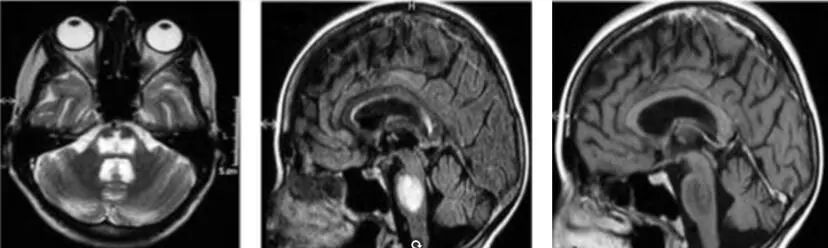

慢性低钠血症患者快速补钠后,逆转细胞内外渗透梯度,引起脑细胞脱水及萎缩,从而引起中央脑桥脱髓鞘症(图1)。临床表现:在原发病基础上,突然出现四肢弛缓性瘫痪,咀嚼、吞咽及言语障碍,眼球震颤,眼球协调运动障碍,缄默,完全或不完全闭锁状态。预后差,死亡率极高,数日-数周内可以导致死亡。治疗:支持、对症治疗为主。甘露醇、速尿、大剂量激素冲击治疗、高压氧、血浆置换治疗。2007年低钠血症指南要求24小时内钠浓度增加小于10-12mmol/L,48小时内增加小于18mmol/L。

图1 渗透性神经系统脱髓鞘疾病脑部病变